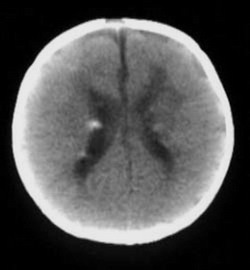

I just looked at her CT scan, and I'm truly amazed that this has gone on for so long. I've dealt with these issues before, and I've never seen them get to this point. A brain CT that looks like hers, is not only tragic, it's comical.

She has no cerebral cortex. Most of her brain has atrophied from the hypoxic insult, and essentially, she survives because her brainstem is still functional. This image, along with her flat eeg (not surprisingly, she has no cortex), would have been far more than enough evidence to "let her go", where I worked in an ICU.

I wonder how forceful the doctor's were with the parents. Obviously, they are at fault for allowing this travesty to continue for so many years.

Compare the following two images. Any moron can see the difference.

Truly sad.Experienced Community organizer. Yeah, let's choose him to run the free world. It will be historic. What could possibly go wrong...